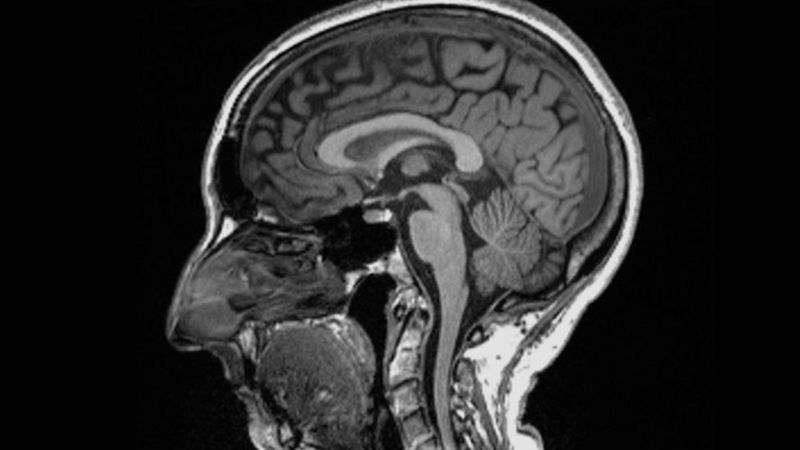

Los investigadores hallaron diferencias significativas en las resonancias magnéticas hechas antes y después de la infección.

Incluso después de una infección leve, las imágenes mostraron que el tamaño total del cerebro se había reducido ligeramente, con menos materia gris en las regiones relacionadas con el olfato y la memoria.

- El tamaño general del cerebro en los participantes infectados se había reducido entre un 0,2 y un 2%

- Hubo pérdidas de materia gris en las áreas olfativas, vinculadas al olfato, y en regiones vinculadas a la memoria.